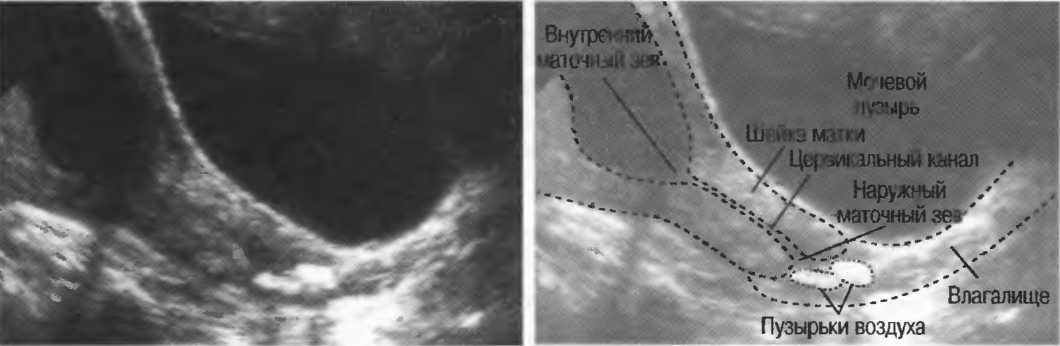

Рис.20б. Реверберации: линии, появление которых обусловлено множественными отражениями от пузырьков воздуха, расположенных между датчиком и поверхностью тела. Артефактные структуры от газа могут экранировать подлежащие структуры в результате поглощения, косого отражения и преломления ультразвука.

Реверберации могут полностью менять изображение, создавая линейные структуры или зеркальное отображение. Например, реверберации между параллельными слоями подкожных тканей создают параллельные линейные структуры в мочевом пузыре (рис. 20в).

Рис.20в. При сканировании матки через наполненный мочевой пузырь параллельные датчику слои тканей передней брюшной стенки могут вызывать появление ревербераций, которые определяются как зхоструктуры в передних отделах мочевого пузыря на фоне анэхогенной полости. Поперечный срез (слева) отличается от продольного среза (справа) при изменении положения датчика.